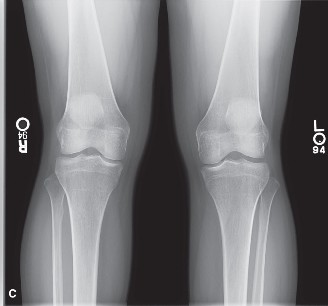

CASE 1 A 22-year-old, female jogger presents complaining of right knee pain. She describes an insidious onset of her symptoms during the last 3 months. She enjoys running most days and is training for a five-mile road race. Recently, she has been running more and has added hill training. Her pain is centered around the patella with little swelling. She has crepitus and pain when climbing stairs or getting out of a chair. X-rays are shown in Figure 9–1A–C.

Figure 9–1 C